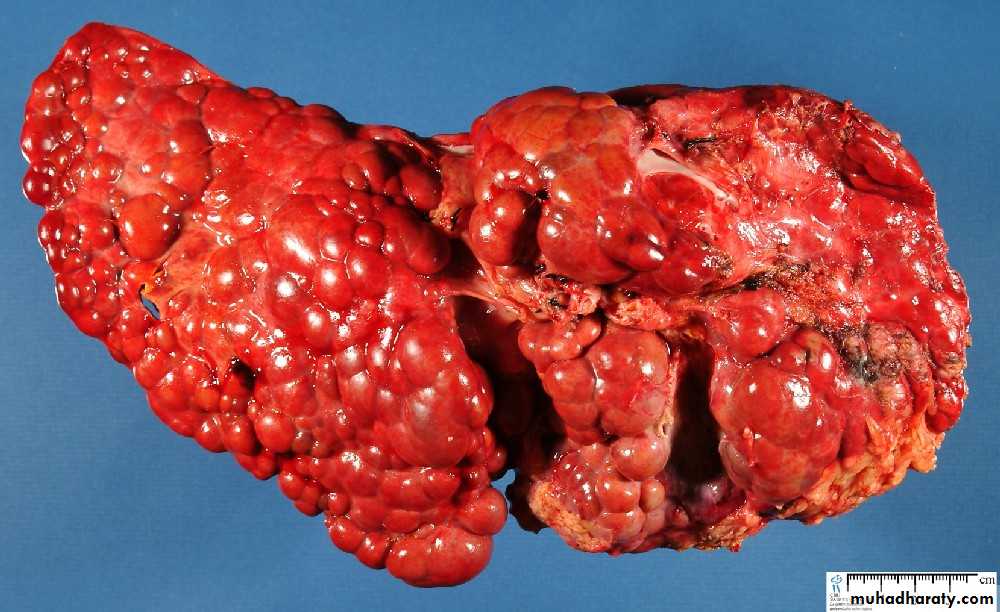

Maconodular cirrhosis the liver is enlarged, firm & nodular. The size of nodule>3mm .

Cirrhosis: loss of architecture of the liver, regeneration nodules which are separated by fibrous tissues septa.

Secondary in the Liver, multiple irregular variable size nodules with central cavitations & necrosis